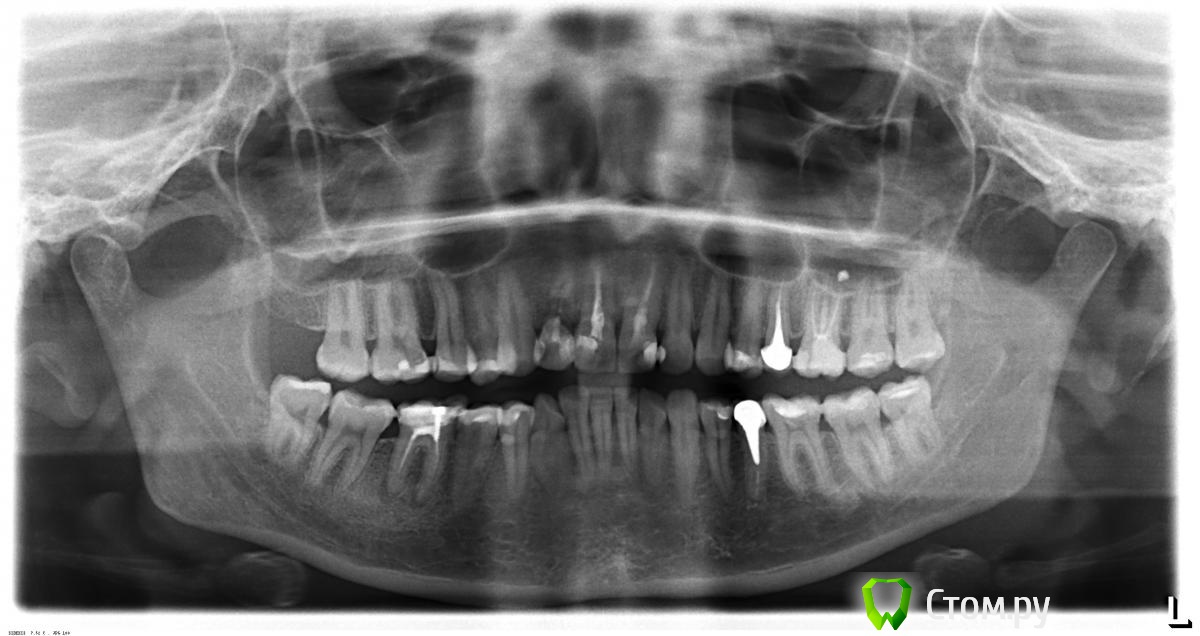

Scrabble Опубликовано 15 июня, 2014 Поделиться Опубликовано 15 июня, 2014 И 46 перелечите в ближайшее время-он тоже требует внимания. Ссылка на комментарий

Novichok78 Опубликовано 16 июня, 2014 Автор Поделиться Опубликовано 16 июня, 2014 И 46 перелечите в ближайшее время-он тоже требует внимания.это который с "винтом"? там мне сказали,что тоже киста, но некоторые врачи говорят перелечивать, а некоторые говорят если не болит не трогай...... ...даже не знаю.... Ссылка на комментарий

faity Опубликовано 17 июня, 2014 Поделиться Опубликовано 17 июня, 2014 Как удалять? я не хочу удалять, удалить проще простого, а вот восстановить (вылечить) ни каждый сможет.......простите, сорвался. делайте КТ, предварительно 1.2 под снос скорее всего, 2.6, 4.6, 1.1 и 2.1 перелечивать и под коронку, 1.6, 2.4, 3.6, 3.4, 4.4, 4.6 перелечиватьортодонт вам в помощь перед всем этим, уточнить план лечения по КТ Ссылка на комментарий